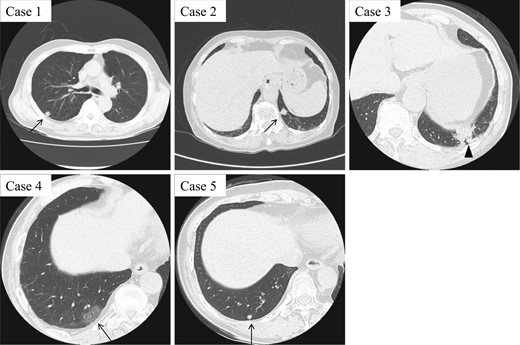

CT findings of five CMPT cases. While Cases 1, 2 and 5 present with small peripheral pulmonary nodules around 10 mm in diameter, Case 4 shows a ground-grass opacity pattern (arrow). Case 3 with mucinous colloid adenocarcinoma exhibits an irregular consolidation-like lesion, which is highly suggestive of lung cancer (arrowhead).

A 66-year-old man with a 45 pack/year smoking history was referred to our hospital with abnormal chest shadow. Chest computed tomography (CT) findings revealed a 10-mm peripheral right lung nodule (Fig. 1). Because frozen sections of the tumor presented borderline lesions with mucinous cystic neoplasm, right upper lobectomy was carried out. Histological findings showed low-grade malignant tumor with ciliated columnar cells and goblet cells (Fig. 2), resulting in a final diagnosis of CMPT. No recurrence has been noted during a 58-month follow-up.

An 82-year-old woman with no smoking history was admitted to our hospital due to abnormal chest shadow. Chest CT findings revealed a 10-mm peripheral nodule in the left S10 segment (Fig. 1). Because lung cancer was strongly suspected, mediastinoscopy followed by thoracoscopic partial resection of the tumor was performed. Frozen sections of the nodule revealed no evidence of malignancy, and CMPT was suspected, confirmed by histological diagnosis (Fig. 2). The patient remained free of recurrence after 55 months.

A 77-year-old man with a 57-pack-year smoking history had an abnormal shadow on routine medical check-up in the left lower lobe (Fig. 1). Lung cancer was strongly suspected, and thoracoscopic left lower lobectomy was performed. Adenocarcinoma was suspected at intraoperative histological consultation, with low-grade malignant tumor including CMPT a possibility. Postsurgical histological findings revealed a transitional or mixed tumor of mucinous colloid adenocarcinoma and CMPT 45 mm in size (Fig. 2). The patient was given oral tegafur-uracil as adjuvant chemotherapy, suspended because of drug toxicity after 6 months. Neither local recurrence nor distant metastasis has been noted at 48 months.

A 70-year-old man with a 92-pack-year smoking history as well as a history of asbestos exposure visited our hospital with a 30-mm peripheral ground-grass opacity (GGO) in the right lower lobe (Fig. 1). Thoracoscopic partial resection of the tumor was performed, and intraoperative frozen section investigation revealed CMPT, which was confirmed by postoperative histological analysis. The tumor showed proliferation of the mucinous epithelium at 15 mm in the subpleural area (Fig. 2). The patient remained relapse-free at 19 months.

A 67-year-old woman was referred with a growing peripheral small lung nodule. She had never smoked but had a medical history of bronchial asthma and eosinophilic pneumonia treated with oral corticosteroid. Chest CT revealed remaining lung nodules with pleural indentation in the S10 segment of the right lung (Fig. 1). Thoracoscopic partial resection was conducted, and pathological diagnosis was CMPT 5 mm in diameter (Fig. 2). The patient remained free of recurrence 28 months postoperatively.